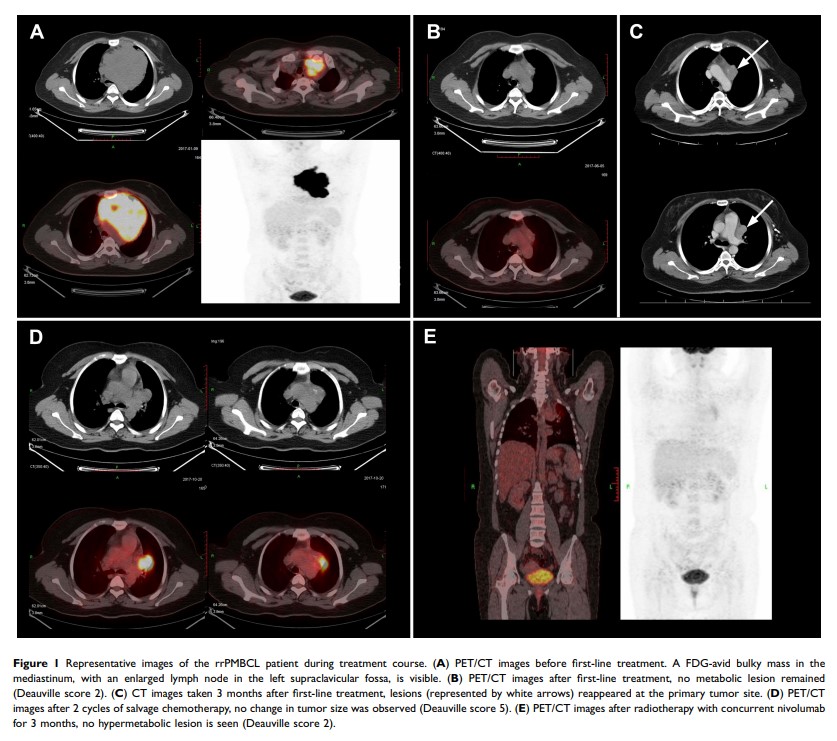

PD-1 抑制剂纳武单抗(nivolumab)与放疗相结合成功治疗难治性原发性纵隔大 B 细胞淋巴瘤患者:一份病例报告和文献回顾